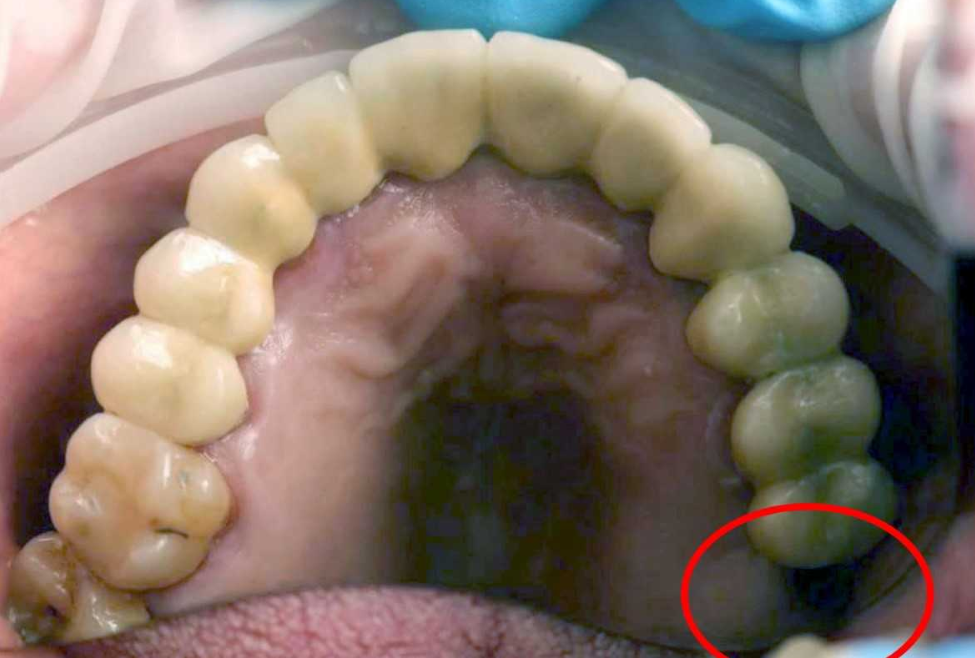

2019年06月12日醫師也覺得匪夷所思!正常小孩大約從6歲開始就會換牙,持續到大約12歲左右才會全換為恆齒。俄羅斯莫斯科一名13歲男童卻很困惑,表示自己原本該長出大臼齒的地方只有凹槽,然後某天又感覺下面很不舒服,找了醫師檢查後竟然發現臼齒長在下面了!

▼醫師取出來後也不禁大開眼界,直呼不可思議!整個醫院的人都覺得這件事太獨特!